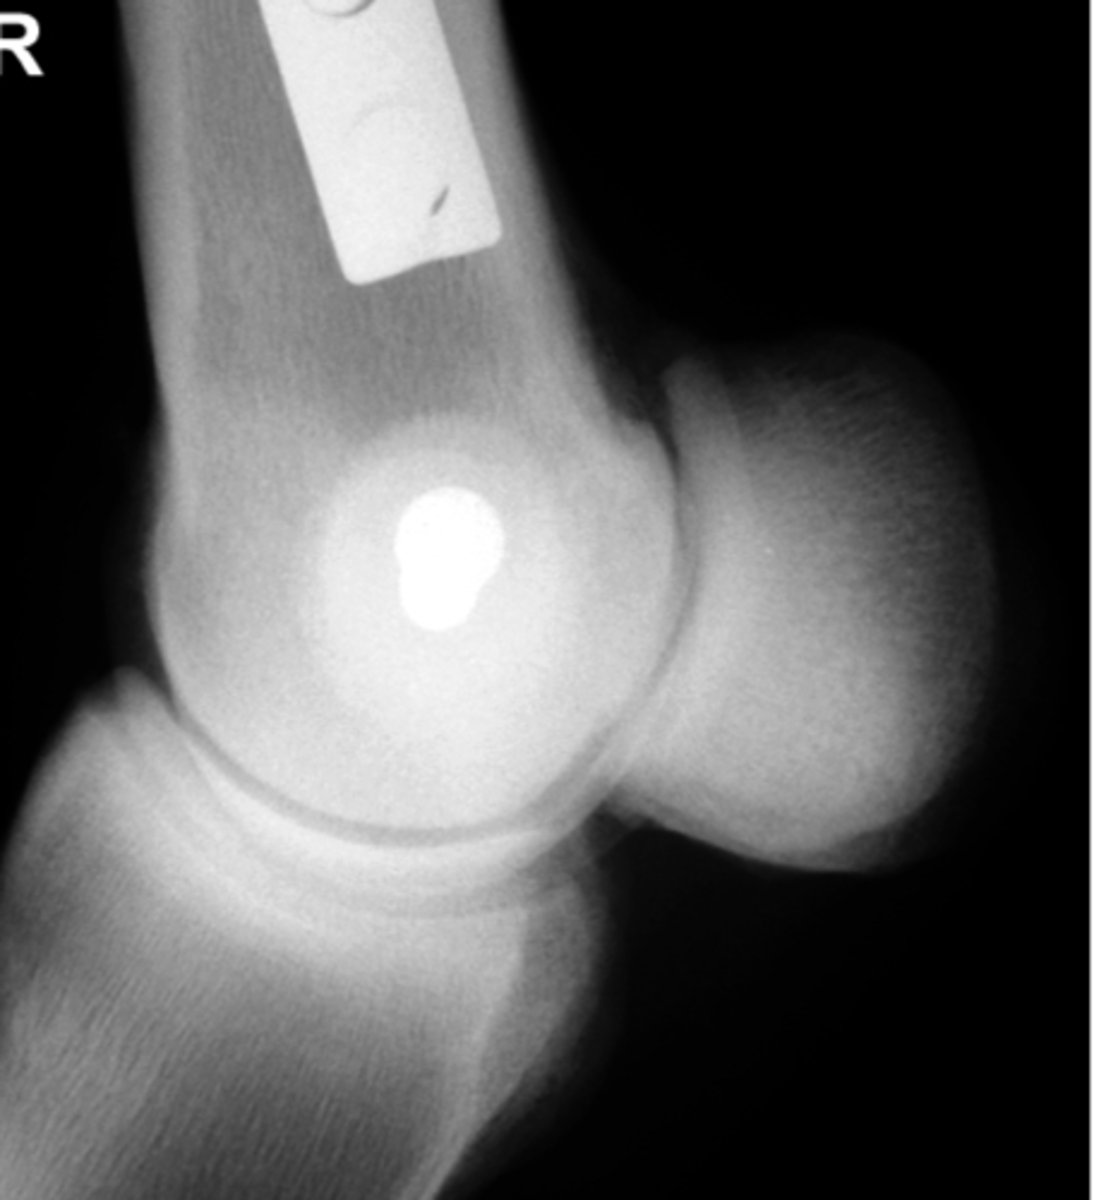

Grade the Salter-Harris fracture?

Grade 2 - fracture through the physis

Above the physis